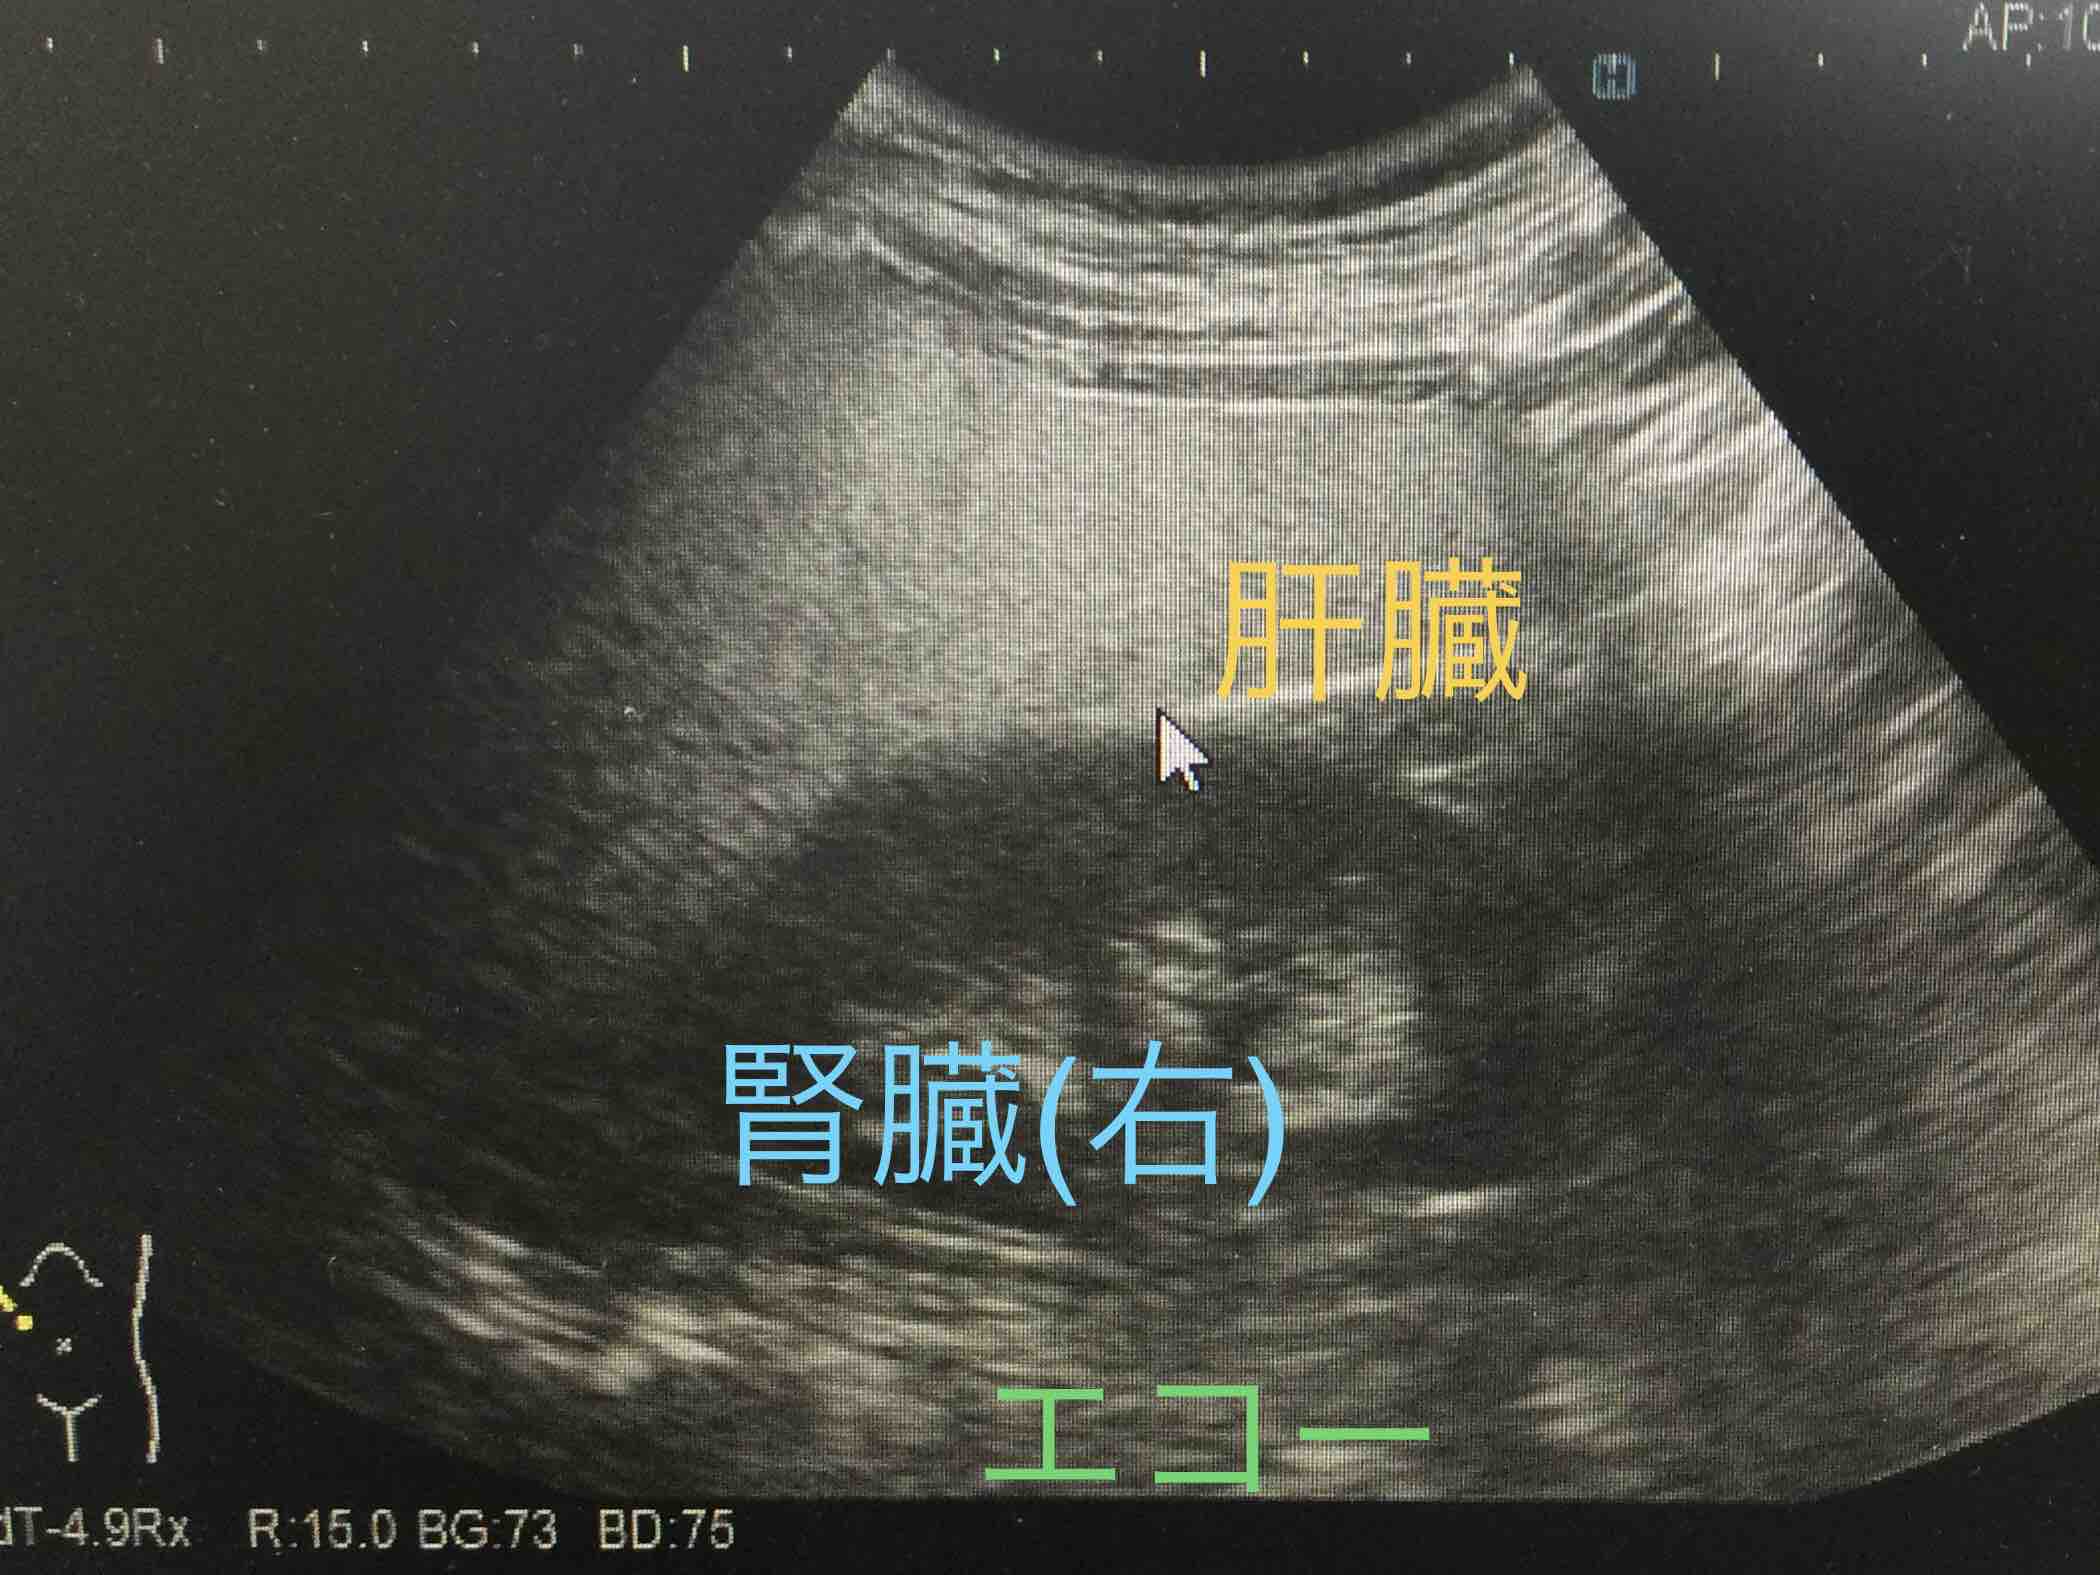

相馬医院 - 腹部エコ。

超音波検査で脂肪肝を,みて,見て,診よう 4。